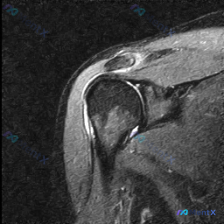

这个肩部MRI影像更支持盂唇病变还是肩峰下撞击综合征?

看到一份肩部MRI T2序列冠状位的病例资料,用户观察到的核心是“盂唇病变”。先放影像分析的重点内容:

- 冈上肌腱在肱骨大结节附着点区域呈明显高信号,肌腱变薄、变细,有回缩迹象

- 肩峰下-三角肌下滑囊区域可见长条状高信号影,提示滑囊积液

- 盂唇形态相对自然,未见明确的巨大撕裂征象

大家觉得这个病例的核心问题是什么?更支持盂唇病变,还是肩峰下撞击综合征?或者两者可能共存?